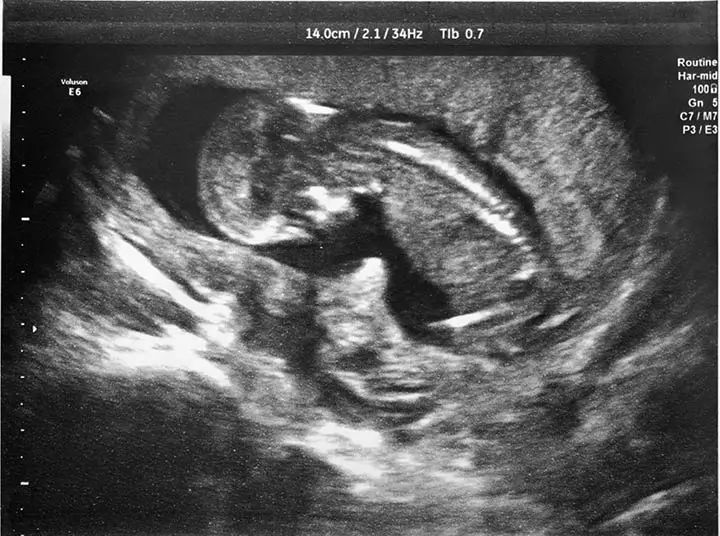

Like the case of a tiny little Chinese newborn girl that came to light recently. What about her? Well, for one, she was already born pregnant! Shocked, aren’t you? Then hold your breath, there’s more to come. Not only was she pregnant, but she was also bearing twins! This happened way back in 2010. A baby girl was born to a couple from Mainland China at the Queen Elizabeth Hospital in Hong Kong with what doctors initially believed were two tumors. On further medical investigation, it was found that the tumors were actually fetuses. Both the fetuses were believed to be of 8 and 10 weeks of gestational age respectively. Both had a pair of limbs, a rib cage, a spine, anus, and intestines. However, both weighed differently – while one of them weighed 14.2 grams, the other weighed around 9.3 grams. Both displayed a tiny umbilical cord that was connected to a placenta-like, single mass. The baby girl had to undergo surgery at three weeks to get those fetuses removed. After she made a good recovery, the baby girl was discharged from the hospital after 8 days of the operation.

According to the doctors, fetus in fetu is that rare condition in which the embryo is externally fertilized and this type of fetus has very low chances of survival. They explained that the fertilization of the twin fetuses that occurred inside the little girl was in all likelihood that of her parents. In simple words, it was probably a case of fertilization occurring at the wrong place. Since the fetuses were too tiny inside an already small fetus, it became extremely difficult to detect their presence during prenatal ultrasounds. The report said that the cause of this abnormality is still unknown. However, it did suggest that one of the probable reasons that can be attributed to it is the mother having undergone multiple abortions. A detailed investigation with some more evidence was required to arrive at a logical conclusion in this case.